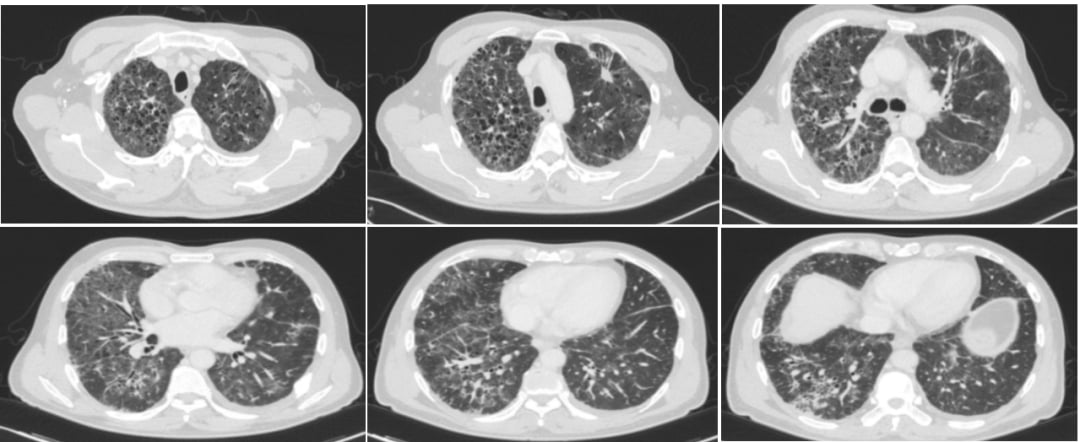

基于基因检测结果,患者于2025年6月开始口服第三代EGFR-TKI——伏美替尼(Furmonertinib)80mg,每日一次。治疗仅仅两个月后,2025年8月11日复查CT显示,患者左肺上叶及肺门区的软组织肿块明显范围局限,双锁骨区、纵隔、肺门、横隔区、腹腔、腹膜后等多发肿大淋巴结均较前缩小,这些都提示肿瘤病灶得到了显著控制。在此期间,患者未出现皮疹、腹泻、肝肾损害等常见不良反应,治疗效果令人满意,为患者带来了巨大的信心。

正当患者和家属沉浸在治疗成功的喜悦中时,挑战不期而至。在伏美替尼治疗有效期间,患者因出现呼吸系统症状就诊。复查CT提示,双肺出现了多发、新发的磨玻璃斑片,高度怀疑是间质性肺炎。结合临床症状、影像学特征,以及排除感染等其他可能原因(气管镜检查及肺泡灌洗液NGS均未见细菌、真菌、病毒等感染),患者被诊断为EGFR-TKI相关性间质性肺炎。